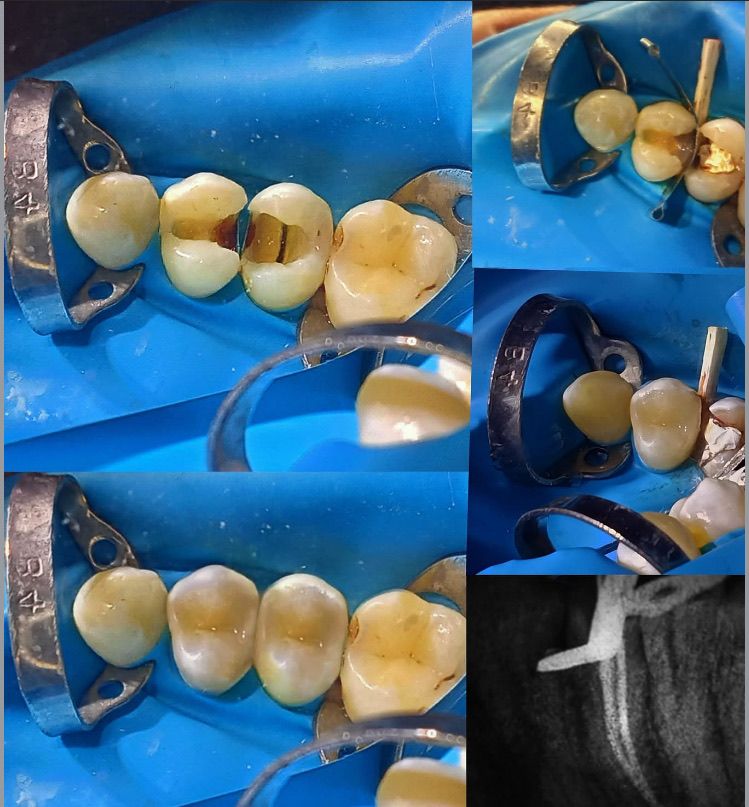

General Dentist with 4 + years of hands - on clinical experience in private and governmental clinics. Skilled in endodontics, restorative dentistry, pediatric cases, and fixed prosthodontics. Known for accurate diagnosis, efficient chairside work, and high patient satisfaction. DHA licensed and available for immediate work